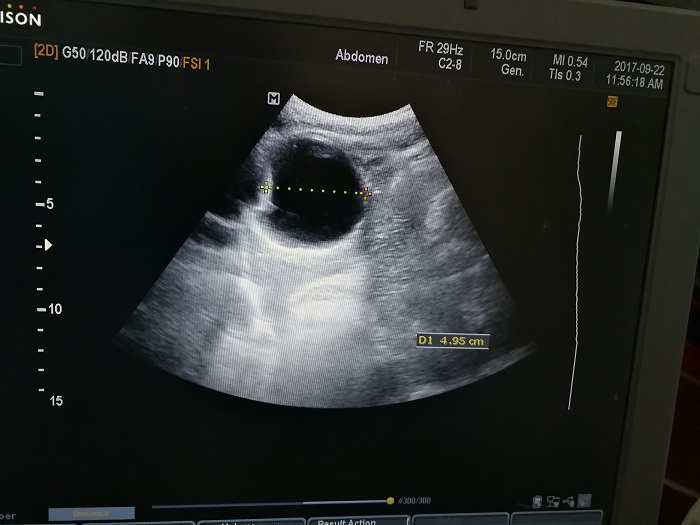

扎西(化名),男,15歲,包蟲(chóng)病篩查陽(yáng)性,牧區(qū)孩子,家里有牦牛20頭、羊200只,狗1條,牛羊自家屠宰,飲用河水。

●革吉縣初級(jí)中學(xué)篩查點(diǎn) · B超現(xiàn)場(chǎng)圖片

除了包蟲(chóng)病篩查外,連續(xù)三天的學(xué)校體檢我醫(yī)療隊(duì)發(fā)現(xiàn)腎積水、腎囊腫、腎結(jié)石的學(xué)生患者較多,我們將體檢到的相關(guān)臟器疾病同時(shí)間反饋給了班主任,讓他們密切觀察病情,及時(shí)通知家長(zhǎng)。劉冬梅醫(yī)生建議,學(xué)校要組織學(xué)生多飲水,同時(shí)多加觀察本地水質(zhì)情況。

本次篩查,革吉縣初級(jí)中學(xué)共篩查學(xué)生498例,陽(yáng)性3例,疑似2例。